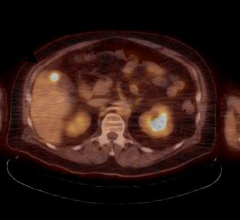

Learn more about GenIQ, a new post-processing application for assessing the vascular properties of brain, liver, prostate and breast tumors for initial as well as follow-up examinations.